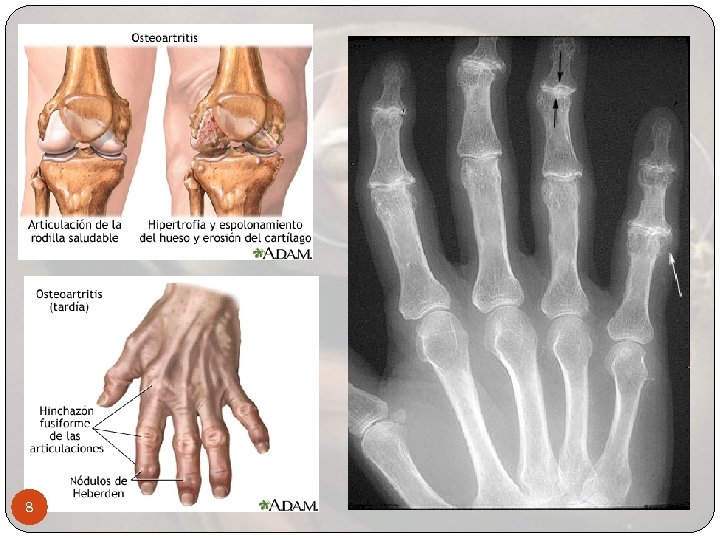

8

Diagnóstico de la osteoartritis El diagnóstico se basa en el historial clínico y un examen físico. Radiografias o resonancia magnetica (MRI) para descartar otras causas de dolor y para determinar la extensión del daño. Una radiografía de las articulaciones afectadas mostrará pérdida del espacio articular. En casos avanzados, habrá un desgaste de los extremos del hueso y espolones óseos. La aspiración articular, procedimiento en el que se obtiene y analiza el fluido articular (liquido sinovial) afectadas Ningún examen de sangre sirve para diagnosticar la osteoartritis 12

Diagnóstico usando el historial clínico y examen físico Movimiento articular que puede causar un sonido 13 crepitante (chirriante), llamado crepitación Inflamación articular Rango limitado de movimiento Sensibilidad al presionar la articulación El movimiento normal con frecuencia es doloroso